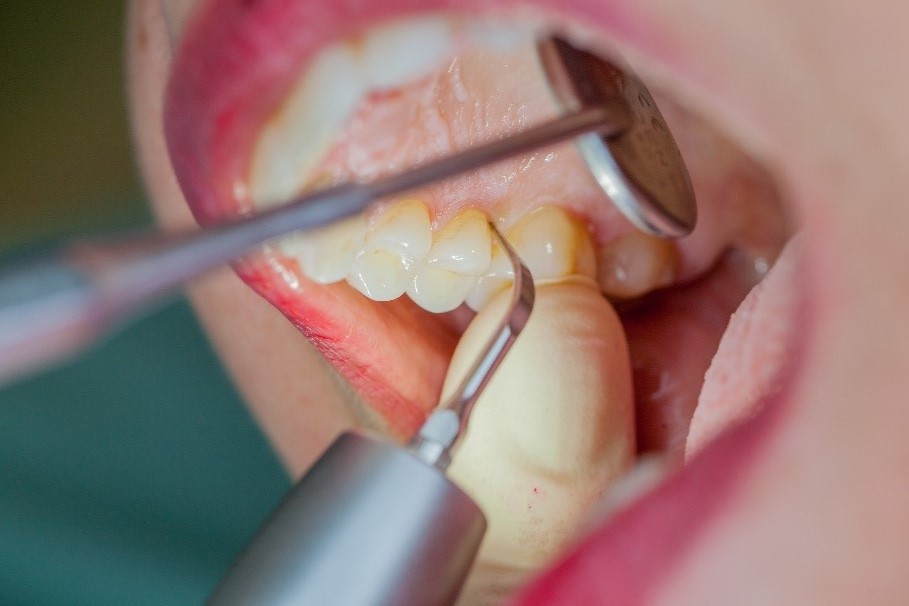

Where necessary, initial periodontal treatment is carried out. First, professional tooth cleaning establishes healthy gingival conditions. In this procedure, calculus (Fig. 1) and biofilm (Fig. 2) are removed as far as the gingival sulcus. In combination with careful instruction on oral hygiene, this gives the patient the basis for long-term freedom from inflammation.15

Rotary cleaning with prophylaxis polishing cups and brushes

Fig. 2: Rotary cleaning with prophylaxis polishing cups and brushes (W&H Proxeo prophylaxis contra-angle handpiece) ensures smooth surfaces on teeth. It enables patients to check biofilm effectively at home.